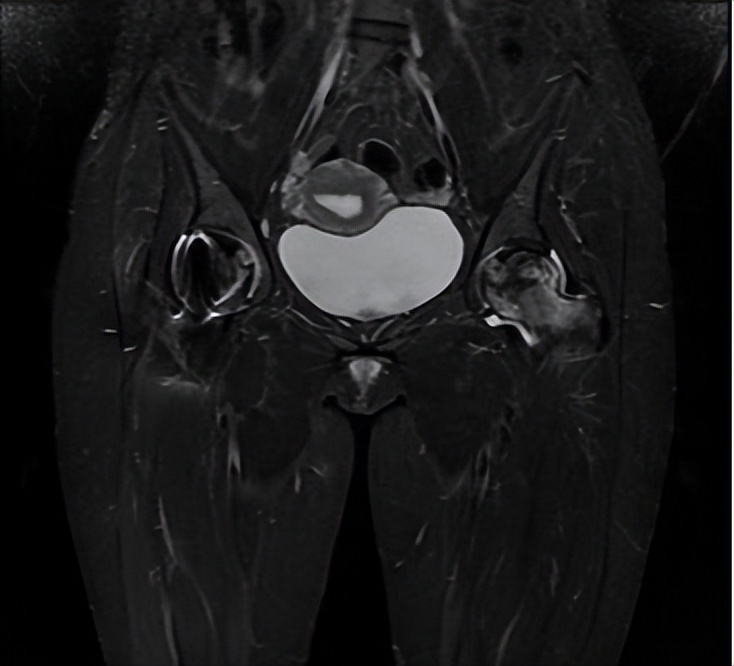

图为左侧疼痛5月后磁共振,可见左侧股骨近端明显水肿

2022年3月22日,阿依右侧保髋手术顺利进行,术后恢复良好,但在术后5个月复查时,阿依主诉左髋疼痛加重,X片显示股骨头轻微塌陷,MR检查左股骨近端明显骨髓水肿。有了右侧股骨头保髋手术的体验,阿依主动提出,左侧也接受保髋手术。8月12日为阿依的左侧进行了保髋手术,术中打开关节后,却有了意外的收获。